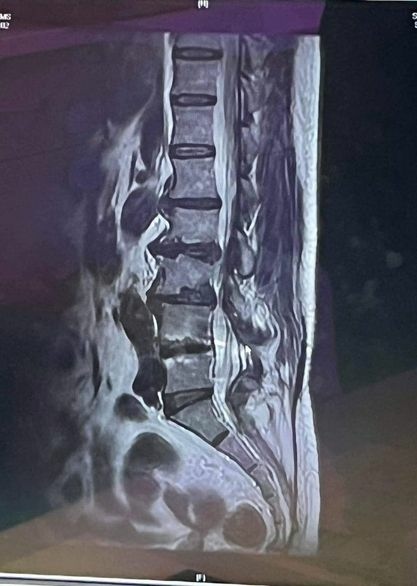

協助脊柱壓迫神經客戶申請勞保給付:

$176,000💰💰💰

#脊椎壓迫神經的權益你知道嗎?

脊柱壓迫神經後遺症

爭取金額:$176,000💰💰💰

許小姐因脊椎壓迫神經造成腰部疼痛及雙腳無力無法行走,必須由老公攙扶及坐輪椅,只好求診醫院,醫生詳細檢查完後建議她開刀以減輕疼痛,雖然目前能夠行走,不過還是留下永久後遺症。